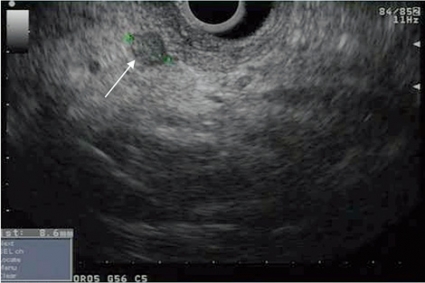

Den vanligaste submukösa tumören är gastrointestinal

stromacellstumör (GIST), som utgår ifrån muscularis propria eller muscularis mucosae (Figur 4). Vid storlek >3 cm, oregelbundna kanter och heterogen ekogenitet ökar risken för malignitet, men det kan vara svårt att skilja mellan benign och malign GIST endosonografiskt, och då kan man ta vävnadsprov med EUS-FNA eller vävnadsbiopsi för cytologisk analys av mitotiskt index. Immunhistokemisk analys hjälper inte bara till med diagnostiken av GIST, utan underlättar också differentialdiagnostiken mot andra ovanligare tumörer såsom leiomyom, leiomyosarkom och schwannom. En diagnostisk markör för GIST är c-Kit (CD117), medan desmin och S-100-protein är vanligare uttryckt i leiomyom, leiomyosarkom och schwannom.